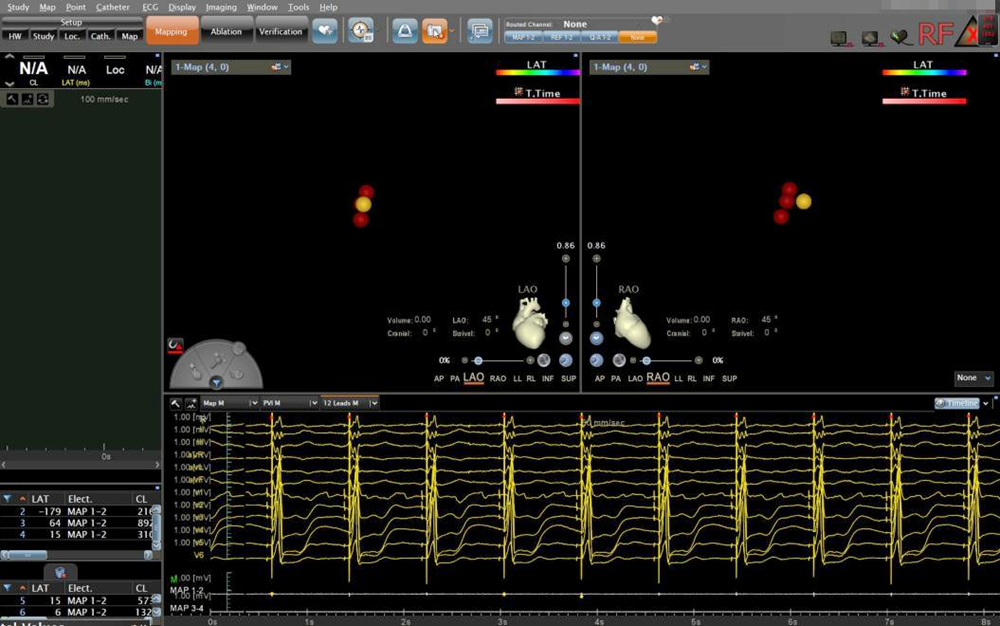

▲房室结消融靶点图及腔内心电图

术中实时测试显示,达峰时间由术前141.67ms缩短至术后52.78ms, QRS波时限由术前200ms缩短至术后122ms,心脏再同步化效果立竿见影,且未出现膈肌刺激等并发症,后考虑到患者同时伴有心房颤动,为了提高双心室起搏比例、控制心室率、降低心律失常的发生,遂决定继续行房室结消融术。